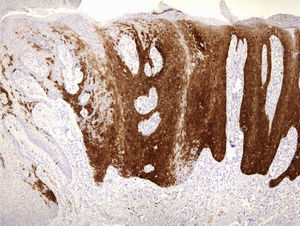

En la exploración se observaba una lesión periungueal exofítica, de 0,7cm de diámetro, de coloración rojo-grisácea y de superficie hiperqueratósica (fig. 1). El estudio anatomopatológico mostraba una epidermis hiperplásica, con pérdida de la arquitectura celular normal, atipia citológica moderada, disqueratosis y coilocitos en la epidermis (fig. 2); además de una sobreexpresión de la proteína de supresión tumoral P16 (fig. 3). Con el diagnóstico de una papulosis bowenoide (PB) extragenital se reinterrogó al paciente, quien negaba antecedentes de verrugas en la zona genital/anal, así como en su pareja actual. Se realizó un estudio analítico con recuento linfocitario incluyendo CD4 y CD8 y la serología para el VIH, que resultó normal. La captura de híbridos de la lesión fue positiva para el serotipo virus del papiloma humano (VPH) 42. Se decidió hacer una extirpación completa de la lesión y controles periódicos, que incluyeron a su pareja sexual, estando asintomático al año del diagnóstico.

La histopatología es similar a la de la EB, observandose en la PB la presencia de cambios más focales y menos intensos1,5,6. El diagnóstico diferencial entre estas 2 entidades requiere siempre un correlato clinicopatológico.